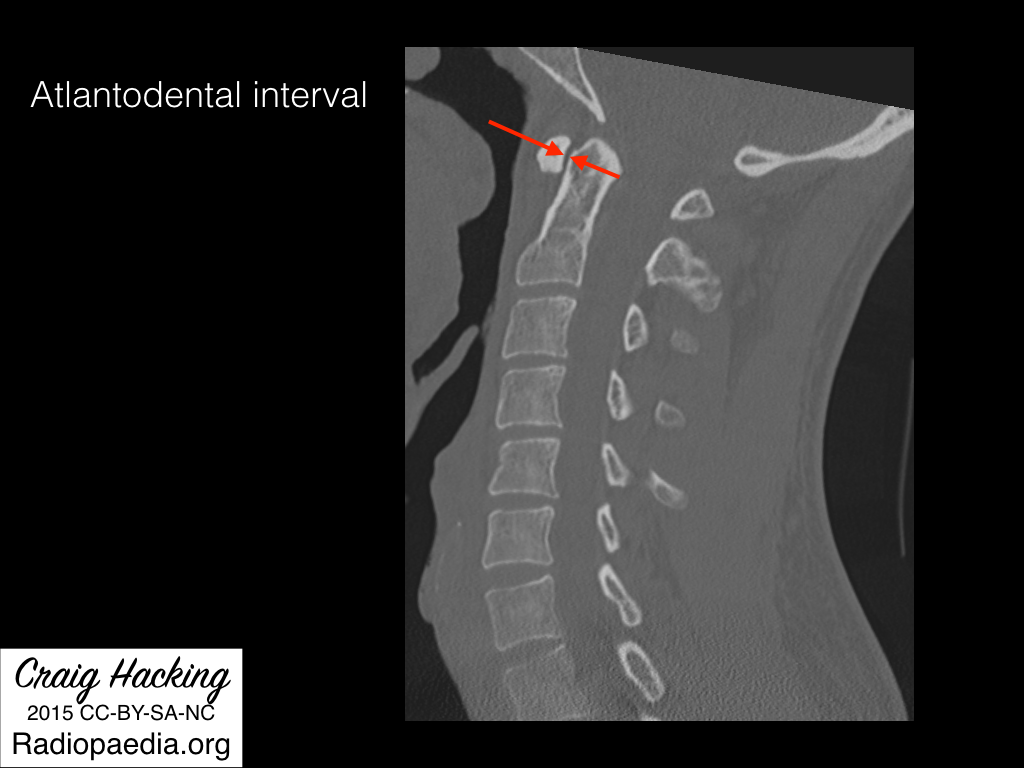

Atlantodental interval

• Basically space between anterior aspect of dens and posterior aspect of C1

• Normal

• < 3 mm on XR

• < 2 mm on CT

• Widening of the atlantodental interval is highly suggestive of transverse ligament injury